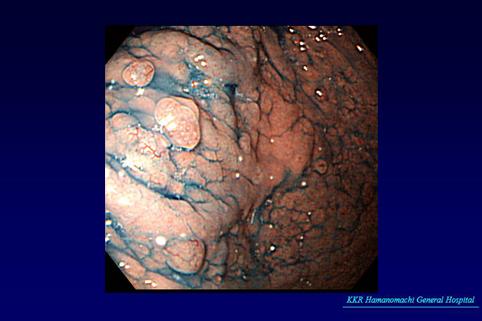

질환(병리주체)의 분류 카시노이드종양/

부위(장기별) 위(부위)/2개 이상

검사방법 내시경

종양의 최대경(밀리미터) 1~9

종양의 심달도 sm

다발종양(동일 장기) 유(동시성)